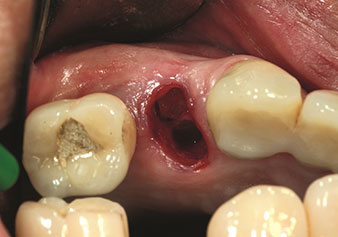

One application, which is often underestimated is the atraumatic extraction of tooth roots or root fragments in the scope of alveolar management. The fine periotomes, which are currently available in two versions (EX1 and EX2 from W&H), can also be used to remove teeth which have previously undergone special endodontic treatment or ankylosed roots with ease. This results in extraction alveoli where both the hard and soft tissue are fully intact as it is generally possible to avoid reflection.

This establishes the optimal basis for subsequent or immediate implant treatment (Figures 1 and 2 included with the kind permission of Dr Torsten Conrad, Bingen a. Rhein).

Photo: © Dr Torsten Conrad (Bingen a. Rhein)